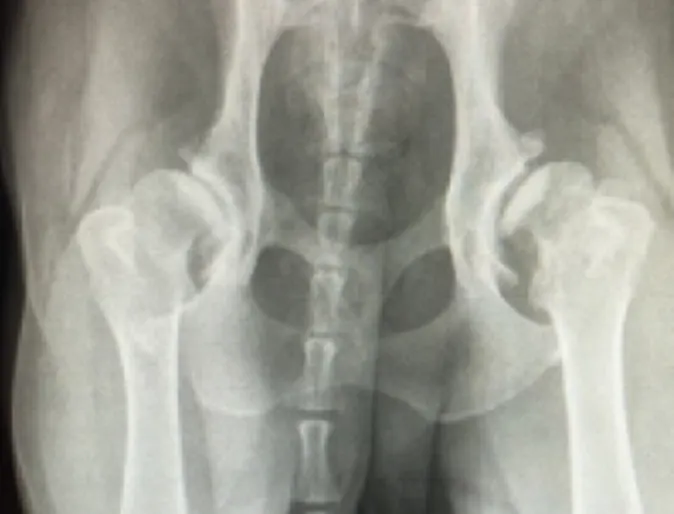

Canine Hip Dysplasia

Canine Hip Dysplasia (CHD) is a developmental disorder of the hip that begins withjoint laxity and progresses to arthritis over a period of several months to years